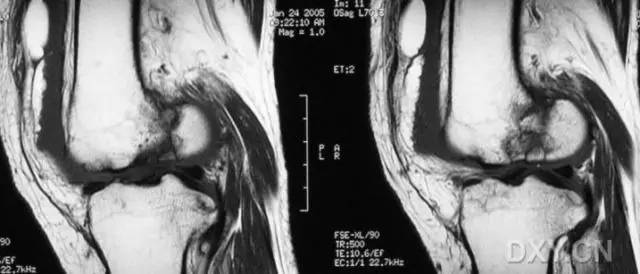

8. Segond 骨折和反向 Segond 骨折

(1)Segond 骨折

是发生在胫骨平台外侧的垂直撕脱性骨折。这种骨折在前后位 X 线片上显示最佳。屈曲位时膝关节受到内旋暴力作用,导致皮质骨撕脱性骨折,这种骨折常发生在运动员身上。

常引起股骨内髁和胫骨平台后内侧骨挫伤,75%~100% 的患者伴前交叉韧带断裂,33% 的患者伴外侧半月板损伤。

一位足球运动员的 Segond 骨折。A 正位片示关节线下方胫骨外侧皮质撕脱(箭头)。B MRI 冠状位 T1 加权像示附着于髂胫带的骨折碎片(空箭头)(来源:Radiol Clin N Am 53 (2015) 737–755,YU,Ohio)

(2)反向 Segond 骨折

胫骨平台内侧皮质骨撕脱性骨折,被称为内侧 Segond 骨折或反向 Segond 骨折。这种骨折的旋转机制与 Segond 骨折相反,该骨折与后交叉韧带断裂及内侧半月板损伤相关。

一位足球运动员的反向 Segond 骨折。A 正位片示关节线处的胫骨内侧见一细小骨折片(箭头)。B MRI 冠状位 T1 加权像示骨折片出现在内侧副韧带关节囊附着处(方框)(来源:Radiol Clin N Am 53 (2015) 737–755,YU,Ohio)